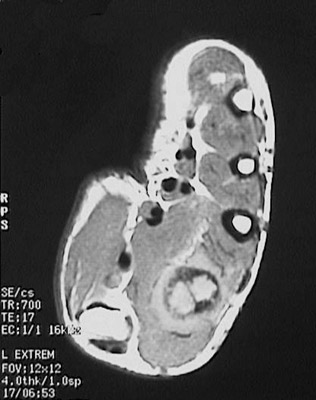

Click on the aneurysmal bone cyst in the MRI above:

The MRI scan of this hand demonstrates an aneurysmal bone cyst of the second metacarpal bone.